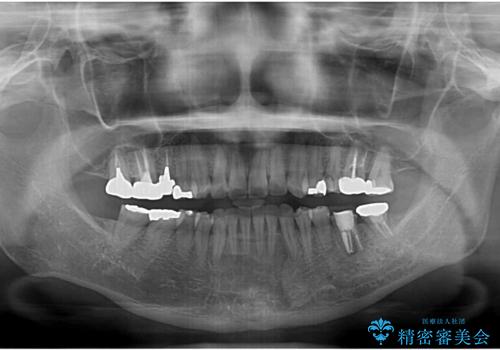

- 高校生の時に行った矯正治療の後戻りと、通院してもなかなか改善しない奥歯の痛みを気にして来院された患者様です。

まずは左下奥歯の根管治療を行い、痛みが引いたことを確認してから矯正治療を開始しました。

後戻りは軽微であったため、インビザライン・ライトにて歯列を整えました。

矯正治療後には、左下奥歯の症状がないことを確認し、セラミッククラウンにて補綴治療を行うこととしました。

矯正治療後のレントゲン写真では、根尖部に認められた病変(骨の溶けていた像)は消失していることが分かりました。